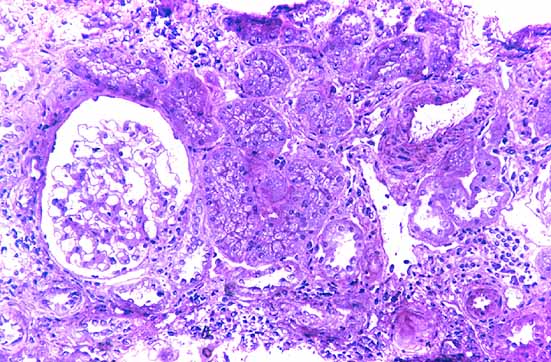

Figura 9. Detalle del infiltrado inflamatorio linfoplasmocitario intersticial entre los túbulos, vasos y glomérulo. M.O.A.R. Fucsina-Azul de Toluidina. 200x |